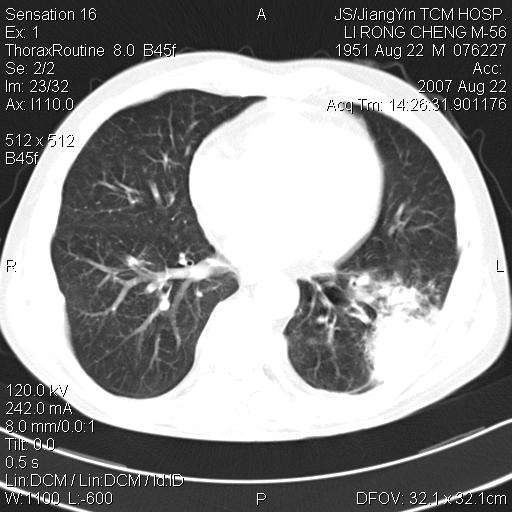

标题: CT9479:M,56Y,DM病史,咳嗽发热5天.肺脓疡.肺癌? [打印本页]

标题: CT9479:M,56Y,DM病史,咳嗽发热5天.肺脓疡.肺癌?

考虑结核,空洞形成,并发支扩

左下肺炎性病变,有支气管扩张,考虑肺结核合并感染。

考虑结核病播散!

1:病灶不是实质肿块形态,胸膜脂肪间隙存在!

2:周围有卫星病灶,不象阻塞性肺炎

3:往下间质增厚,播散征象.

左下肺团片状类软组织密度影,形态不规则,边缘欠规整,其内可见液化区及气体影,病灶内侧见引流支气管影,相邻胸膜反应性增厚。病灶周围肺野内见增粗支气管,壁厚,边缘模糊。考虑:支气管扩张并感染;肺脓肿。